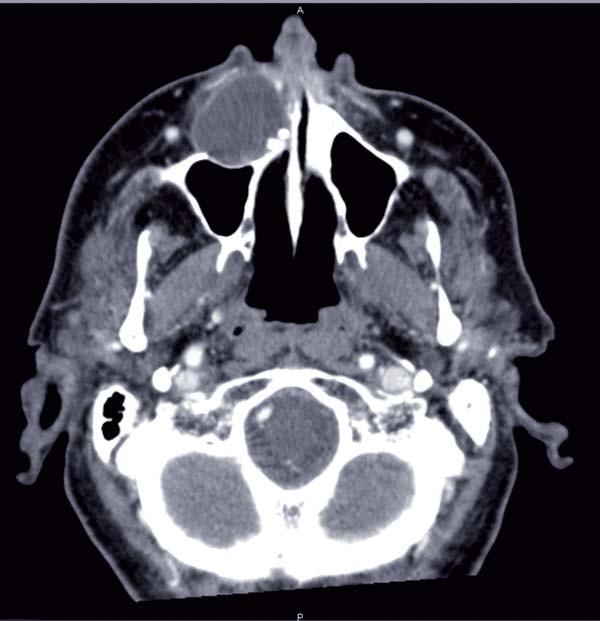

– un scanner du massif facial (fig. 2, 3, 4) a permis d’objectiver un processus expansif hypodense, maxillaire médian et paramédian droit, de 42 mm de grand axe, bien délimité par un liseré dense, aux parois propres, avec une…